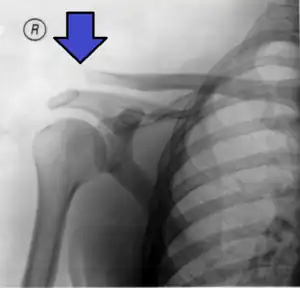

| An Xray showing a separated shoulder. Notice the separation between the end of the collarbone and the scapula. | |

A separated shoulder, also known as acromioclavicular joint injury, is a common injury to the acromioclavicular joint.[2] The AC joint is located at the outer end of the clavicle where it attaches to the acromion of the scapula.[2] Symptoms include pain which may make it difficult to move the shoulder and often a deformity.[2][1]

It is most commonly due to a fall onto the front and upper part of the shoulder when the arm is by the side.[2] They are classified as type I, II, III, IV, V, or VI with the higher the number the more severe the injury.[2] Diagnosis is typically based on physical examination and X-rays.[2] In type I and II injuries there is minimal deformity while in a type III injury the deformity resolves upon lifting the arm upwards.[2] In type IV, V, and VI the deformity does not resolve with lifting the arm.[2]

X-ray indicates a separated shoulder when the acromioclavicular joint space is widened (it is normally 5 to 8 mm),[11]it can be classified into 6 types.